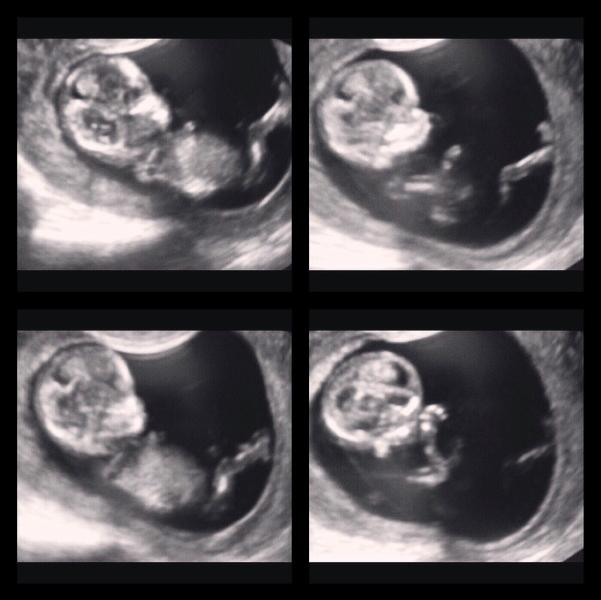

1.08.2016 в 8.40 ПЕРВЫЙ СКРИНИНГ!!!

Через живот посмотреть не удалось т.к загиб матки,короче смотрела как там по умному наверно "трансвагинально"!!!Вобщем смотрит она в монитор и говорит:"Ну что ты мой хороший смотришь на меня вот так 😳,давай переворачивайся!"Поворачивает мне монитор,а он реально просто лупит глазами и все👀😂Вобщем разговаривала она с малышом долго и ласково,говорит ему,тебе носик померить надо....на что он просто её игнорил и был вреднючий как мама☺️Но с врачами шутки плохи☝🏻️так...